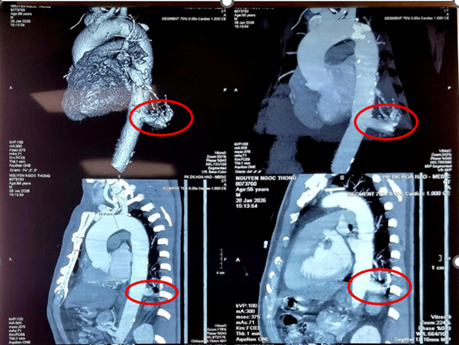

Trường hợp ông N.N.T (56 tuổi, Tây Ninh) là một tình huống hiếm gặp. Ông tình cờ phát hiện tổn thương thùy dưới phổi trái khi đi khám tổng quát. Tại Bệnh viện Bình Dân, các bác sĩ chẩn đoán ông mắc phổi biệt lập nội thùy với khối kích thước 23 mm × 26 mm. Đáng chú ý, động mạch nuôi khối này xuất phát trực tiếp từ động mạch chủ xuống với đường kính lên tới 17 mm – một kích thước rất lớn và đầy rủi ro nếu người bệnh không được điều trị.

Nếu một người có các triệu chứng như viêm phổi tái diễn tại một vị trí, ho ra máu hoặc tình cờ phát hiện khối bất thường ở phổi, hãy đến các cơ sở y tế chuyên sâu để được tầm soát. Chẩn đoán hình ảnh như MSCT có thể phát hiện phần phổi biệt lập.